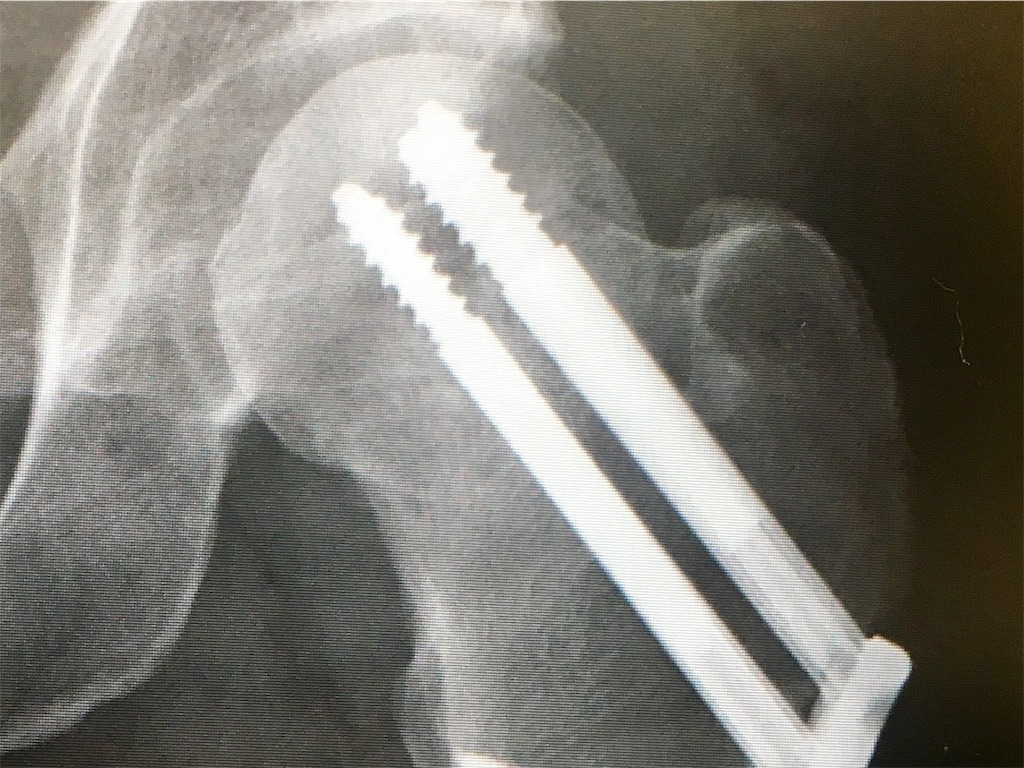

月曜日一ヶ月診断のレントゲン撮影してきました

先月よりさらにモヤモヤが増えてるようで良いんじゃないかな?という感じ

来月のMRIである程度ははっきり分かるようなのですがここ数ヶ月劇的に良くなってる気がします

ただ頸部を繋ぎ合わせるのを優先してるため骨頭が曲がった状態ではあるようで、それによりまっすぐ立てないのと体が屈曲してるようです

が、、やはり自分としては人工関節の処置じゃなくてガタガタでも繋げてくれたことに関しては感謝してるので体の屈曲と足の曲がり方に関しては

まぁしょうがないかなと思ってます

内転筋の痛みも骨頭からズレてるから引っ張られたりして痛いんじゃないかな?という事らしいです